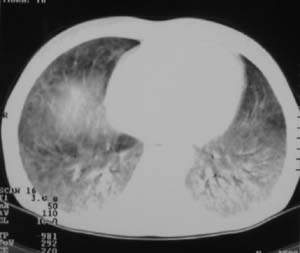

以下是引用zjzjr在2007-9-20 12:29:00的发言:[br]双肺磨玻璃改变,考虑肺水肿.

以下是引用yangzongshan在2007-9-20 18:29:00的发言:[br]两肺毛玻璃样改变,其内可见肺纹理影,无胸腔积液,故考虑肺泡蛋白沉积症

以下是引用276894491在2007-9-20 13:40:00的发言:[br]考虑肺水肿;外源性过敏性肺炎不排除。

以下是引用逸风在2007-9-20 20:45:00的发言:[br]两肺磨玻璃样改变,临床病史短,发热,考虑病毒感染合并右肺代偿性肺气肿.待排肺水肿,病史短,不支持肺泡蛋白沉着症.